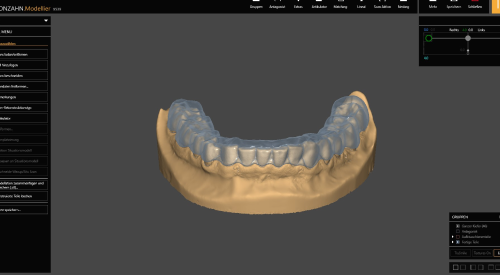

Szyny, które wykonuję, są frezowane z wysokiej jakości akrylu (PMMA). Nie stosuję metod odlewania czy druku 3D, co gwarantuje najwyższą precyzję i trwałość.

Moje szyny to nie tylko narzędzie korekcyjne, ale kluczowy element całościowej terapii, mającej na celu przywrócenie pełnej funkcjonalności narządu żucia i poprawę ogólnego stanu zdrowia pacjenta.